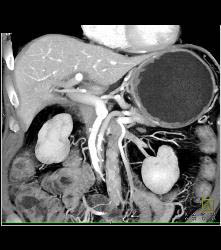

Antral Carcinoma